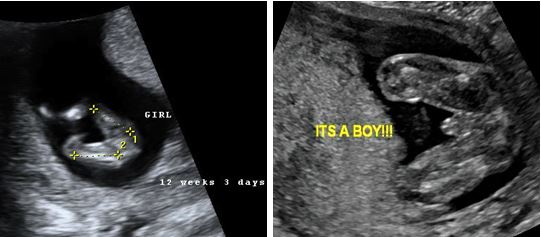

Zhvillimet në mjekësi dekadat e fundit, që në vitet ‘80, ‘90 dhe në vitet 2000, sidomos me aplikimin e teknologjisë së informacionit, teknologjisë elektronike dhe zhvillimet galopante në disiplinën e imazheri diagnostikës, pati ndikim thelbësor edhe në imazherinë diagnostike në obstetrikë, pra në ndjekjen e shtatzënisë. Në vendin tonë, ekzaminimet ekografike e kanë zanafillën në vitin 1985, dhe pas viteve ‘90 ekzaminimi ekografik në shtatzëni filloi të gjejë aplikim të gjerë, duke ardhur në ditët tona që nuk imagjinohet ndjekja e shtatzënisë pa ekzaminimin ekografik, megjithëse ky lloj ekzaminimi po merr një rol të tepruar, nëse mund të themi, sepse njohuritë, eksperienca dhe kompetenca profesionale e mjekut, në këtë rast mjekut obstetër gjinekolog, nuk mund të zëvendësohet me një ekzaminim ekografik, ku, sipas shumë protokolleve perëndimore mjekësore, bëhen 1 deri në 4 ekzaminime ekografike përgjatë gjithë shtatzënisë.

Sikurse u theksua më lart, zhvillimet e vrullshme të teknologjisë dhe aplikimi i teknologjisë në mjekësi, imazheri, respektivisht ekzaminimet ekografike në shtatzëni, kanë bërë që të përftohen imazhe të qarta të fetusit në mitër, duke e ngritur ndjekjen e shtatzënisë në nivele superior klinike dhe shkencore. Përftimi i imazheve në 2, 3 apo 4 dimensionale – duke i parë imazhet fetale në kohë reale, bën që të përftojmë shumë të dhëna të anatomisë fetale, që nga truri/koka, skeleti, trupi dhe ekstremitetet fetale.

Në këtë kontekst, paralelisht me këto zhvillime, u rrit edhe dëshira për informacion nga ana e pacientëve, prindërve të ardhshëm apo deri familjarëve të pacientëve, falë kjo edhe nga informacioni i aksesueshëm në masë nga njerëzit, për të dhëna/informacione online, e thënë më thjeshtë për t’u kuptuar më mirë, në internet. Në vazhdim të informacionit optimal të përftuar nga klinicistët në ekzaminimet imazherike në shtatzëni që në tremujorin e parë, ku edhe ka përfunduar formimi i përgjithshëm i organeve dhe rrjedhimisht pas javës së 10-të, referuar ditës së parë të periodave të fundit, mund të vizualizohen mjaftueshëm mirë organet fetale, por që një vlerësim më të hollësishëm e kërkojnë në ekzaminimin e javës 11-13 të shtatzënisë dhe pastaj në ekzaminimin ekografik në shtatzëni në muajin e 5-të, rreth javës së 20 të shtatzënisë, që quhet edhe ekografia anatomike fetale ose ndryshe ekografia morfologjike fetale.

Pra, që pas javës së 10 të shtatzënisë (java 11 – 13 + 6 ditë) ne mund të përftojmë imazhe fetale deri në përcaktimin e gjinisë së fetusit, neuroanatomine, vlerësojmë qartë ekstremitetet e fetusit apo strukturën e trupit, mushkëri, zemër, organet abdominale, si stomak, veshka, fshikëzën urinare fetale, që në disa vende të zhvilluan e quajnë ekzaminimi ekografik anatomik/morfologjik i hershëm, referuar ekzaminimit standard që bëhet në javën e 20 të shtatzënisë.

Në fakt ky ekzaminim ekografik nuk e ka në fokus dhe protokoll mjekësor përcaktimin e gjinisë fetale, e cila në shumicën e rasteve vlerësohet në disa javë më vonë, rreth javës së 16 të shtatzënisë, duke patur edhe një diferencim dhe imazh më të qartë të anatomisë së fetusit.